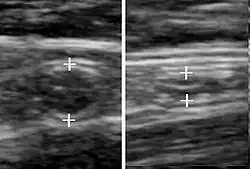

Ultrasound is routinely used in urology to determine the amount of fluid retained in a patient's bladder. In a pelvic sonogram, images include the uterus and ovaries or urinary bladder in females. In males, a sonogram will provide information about the bladder, prostate, or testicles (for example to urgently distinguish epididymitis from testicular torsion). In young males, it is used to distinguish more benign testicular masses (varicocele or hydrocele) from testicular cancer, which is curable but must be treated to preserve health and fertility. There are two methods of performing pelvic sonography – externally or internally. The internal pelvic sonogram is performed either transvaginally (in a woman) or transrectally (in a man). Sonographic imaging of the pelvic floor can produce important diagnostic information regarding the precise relationship of abnormal structures with other pelvic organs and it represents a useful hint to treat patients with symptoms related to pelvic prolapse, double incontinence and obstructed defecation. It is also used to diagnose and, at higher frequencies, to treat (break up) kidney stones or kidney crystals (nephrolithiasis).[42]

Scrotal ultrasonography is used in the evaluation of testicular pain, and can help identify solid masses.[43]